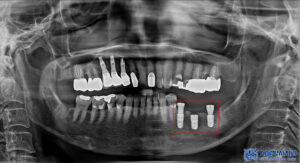

그래서 먼저 왼쪽 아래 상실된 부분의

무절개임플란트 3개를 식립 하기로

계획을 수립하였습니다.

무절개 임플란트

3개 식립을 진행했습니다.

아래쪽의 보철이 마무리된 후,

발치했던 부분의

뼈이식을 포함한 무절개임플란트를

식립 하였습니다.

이때, 골다공증 주사제 시기 또한

본원에서 체크 및 조정하여

안정적으로 수술을 진행하였습니다.